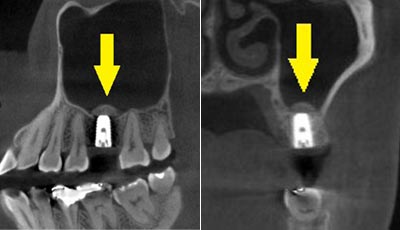

移植した骨が周囲の骨と、結合したのを待ち、6か月後に、インプラント埋入手術を行いました。下の写真が、インプラント埋入後のCT画像で、黄色矢印に示すように、インプラントが2本埋入できました。

移植した骨が周囲の骨と、結合したのを待ち、6か月後に、インプラント埋入手術を行いました。下の写真が、インプラント埋入後のCT画像で、黄色矢印に示すように、インプラントが2本埋入できました。

インプラント埋入後の、別な方向からみたCT画像です。神経の通る管にややギリギリでしたが、神経は傷つけずに、インプラントが埋入できました。この後、4か月ほどで、咬む歯の部分、上部構造を完成させました。

インプラント埋入後の、別な方向からみたCT画像です。神経の通る管にややギリギリでしたが、神経は傷つけずに、インプラントが埋入できました。この後、4か月ほどで、咬む歯の部分、上部構造を完成させました。